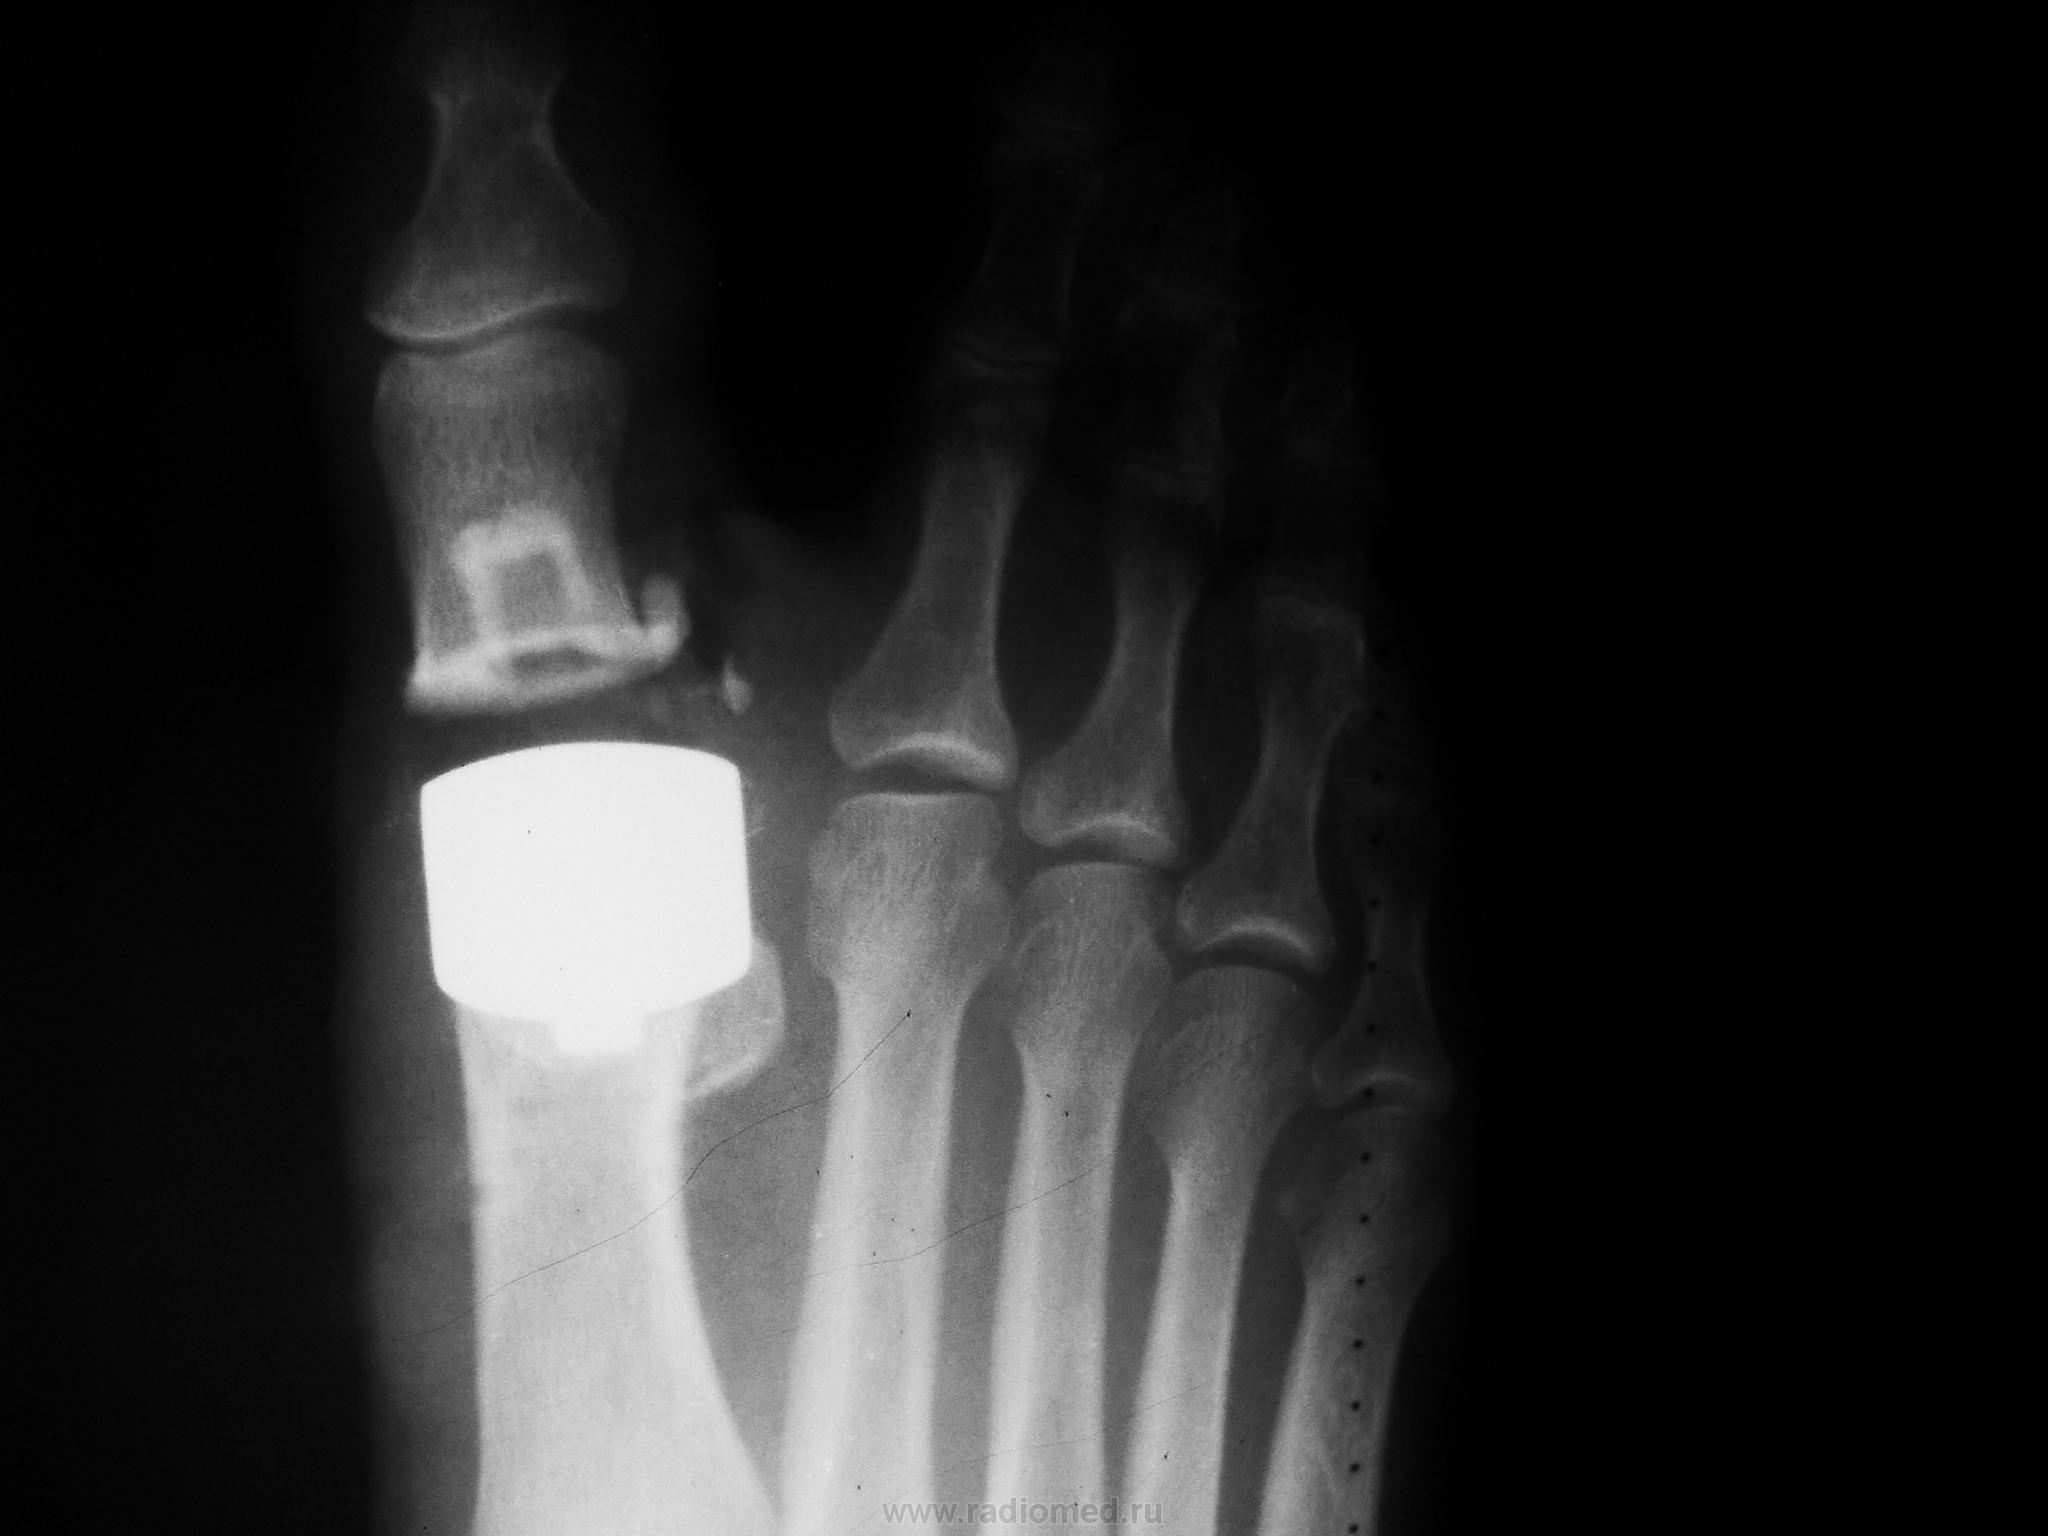

Один из методов лечения поперечного палоскостопия с выраженым дефартрозом 1 пл-ф суст. Операция Вредена-Мейо+ операция Брандеса+формирование поперечной связки стопы+протезирование. Померяйте какой сейчас Hallux valgus, опишите состояние культи и протеза.

2. Трактуйте картину какова она есть, желательно - как можно детальнее. Как там с отеком еще будет: спадет- не спадет, восстановится ось - не восстановиться - Вы свое дело сделали, а это главное.